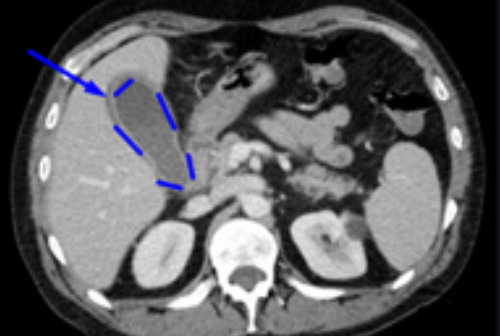

Компьютерную томографию при диагностике хронического холецистита назначают с целью обнаружения возможных осложнений, а также при проведении дифференциальной диагностики.